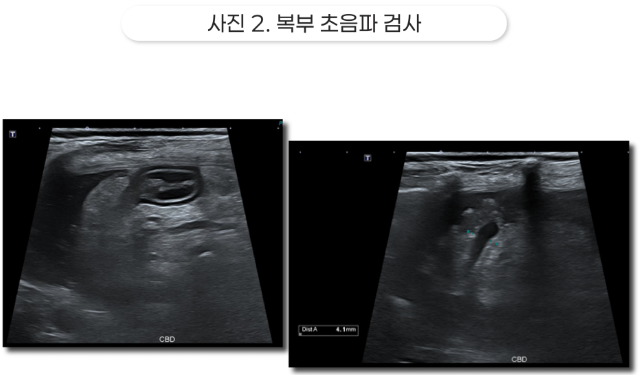

2. 복부 초음파 검사

담낭벽 비후와 점액종 소견을 보이는 담낭, 주변 염증이 나타나고 있음

주변에 나타나는 복수, 확장된 총담관

복부 초음파 검사에서 담낭벽 비후와 grade 6 담낭 점액종, 경도의 총담관 확장, 담낭 주변 복막염 및 복수 소견이 확인되었습니다.

이는 담낭 점액종으로 인한 담낭 파열 소견을 나타냅니다.